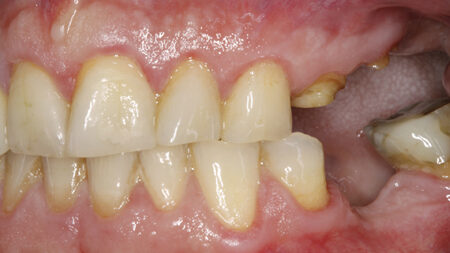

Angulated Implant Placement in the Posterior Maxilla to Avoid Sinus Augmentation and Improve Prosthesis Support: A Case Report

Pollak-fig5 alternate text for this image

Abstract The success of dental implant procedures is dependent on many factors. Overall medical status and health, and economic considerations can be limiting factors in determining which of our patients are appropriate candidates. Additionally, the time required for some implant treatments, and the need to perform bone grafting and augmentative procedures in a staged manner … Read more